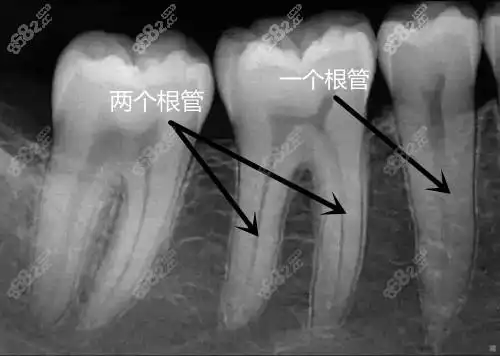

几种因素:根管治疗的价格区间浮动还是比较大的,前牙和磨牙的价格浮动